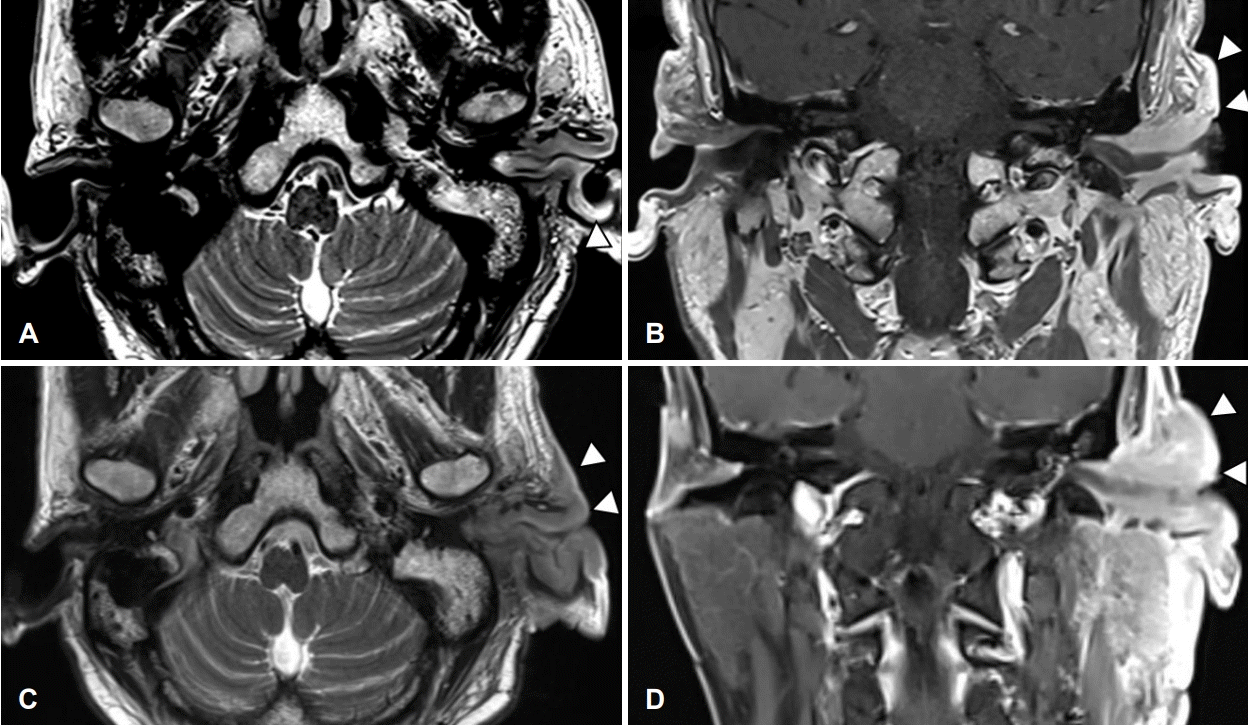

환자 본인의 의사로 타 병원으로 전원 하였고, 본원 최초 내원 두 달 후 타 병원에서 시행한 측두골 자기공명영상에서 좌측 외이도와 이개부 연조직의 부종, 이하선 및 주변 림프절 비대소견으로 염증성 병변과 함께 종양성 상태 의심 소견이 보고되었다(Fig. 4). 재내원 시 병변의 범위는 후이개까지 확장된 악화소견이 관찰되었다(Fig. 2E and F). 환자는 본원에서의 치료 지속을 원하여 양전자컴퓨터단층촬영을 시행하였으며, 좌측 외이도, 이개부 및 이하선을 포함한 불규칙한 과대사성 병변이 관찰되어 악성종양이 여전히 의심되었다(Fig. 5).

MRI of temporal bone. Subepithelial soft tissue thickening in the external auditory canal (cartilaginous portion) and auricle aggravated during antibiotic therapy and daily wound care. A: Post start of treatment day (PTD) 16, T2 weighted image (T2WI) axial. B: PTD 16, T1 weighted image (T1WI) coronal. C: PTD 96, T2WI axial. D: PTD 96, T1WI coronal.